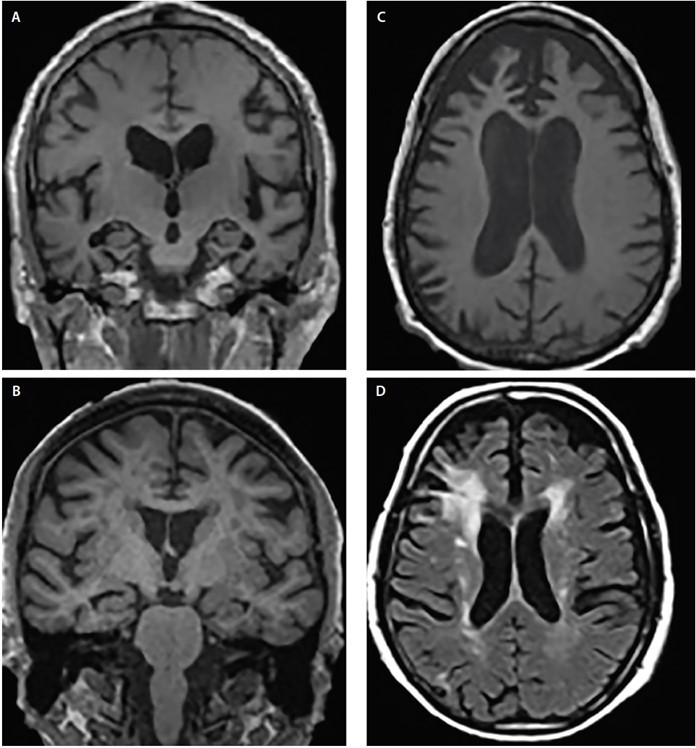

- MRI is commonly used to visualise structural changes in the brain in demented patients; serial MRI is used to monitor disease progression in the patients.

- Besides the routine sequences, other measures of MRI may be used to assess various aspects of neurodegeneration, for example, diffusion tensor imaging MRI (to assess white matter damage), resting-state functional MRI (to assess changes in brain functional connectivity), susceptibility-weighted MRI (to assess vascular activity and identify cerebral amyloid angiopathy).

However, most of these techniques are yet to be applied in routine clinical practice for the assessment of demented patients. Some structural changes in the common forms of dementia are represented in the figure below 11.

Structural atrophy patterns across Alzheimer’s disease (AD) (A), dementia with Lewy bodies (DLB) (B), frontotemporal dementia (FTD) (C) and vascular dementia (VaD) (D). Coronal T1-weighted MRI demonstrates generalised cortical atrophy but differing degrees of hippocampal atrophy in AD (A) and DLB (B). Axial T1-weighted MRI demonstrates bvFTD atrophy with a focal predilection for the medial and lateral prefrontal cortices (C). Axial T2-weighted MRI shows mildly dispersed white matter hypointensities (WMHs), WMHs of the subependymal ventricular lining, septum pellucidum, and confluent periventricular cap and halo WMHs involving the corona radiata and extending into the lateral prefrontal neocortex in VaD (D).